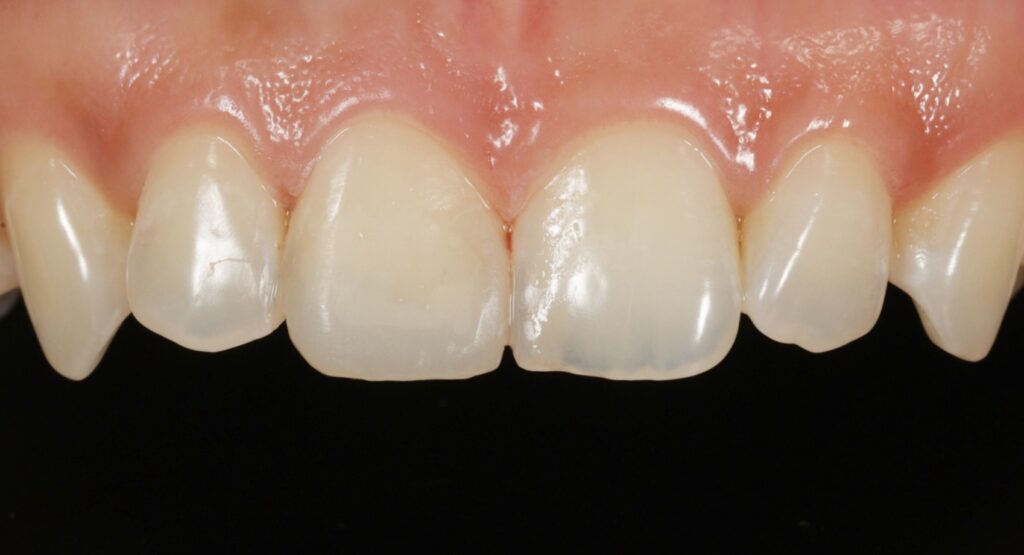

최종 방법,

레진 수복 치료

경과 관찰을 통해 치수가

건강한 상태로 확인되어

레진을 이용한 직접 수복으로

치료를 진행합니다.

레진 치료는 치아를 보존하면서

자연스러운 모습을 재현할 수 있는

장점이 있습니다.

특히 앞니의 경우

심미적인 부분이 중요하므로

절단 부위의 투명도를 재연하는 것이

치료의 핵심 포인트입니다.

여러 가지 색조의 레진을 층별로 쌓아

자연치와 유사한 투명감과

색상을 구현합니다.